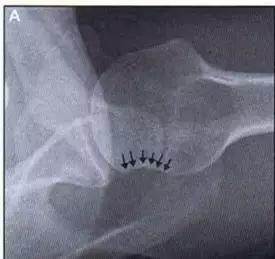

Hill-Sachs 损伤的 X 片(来源:Hill-Sachs Injuries of the Shoulder)

- 肩关节前脱位时发生的肱骨头后外侧凹陷性骨折,是经典的 Hill-Sachs 损伤(Hill-Sachs lesion);

- 而肩关节后脱位时发生的肱骨头前内侧凹陷性骨折,是反 Hill-Sachs 损伤(Reverse Hill-Sachs lesion/ McLaughlin lesion)。